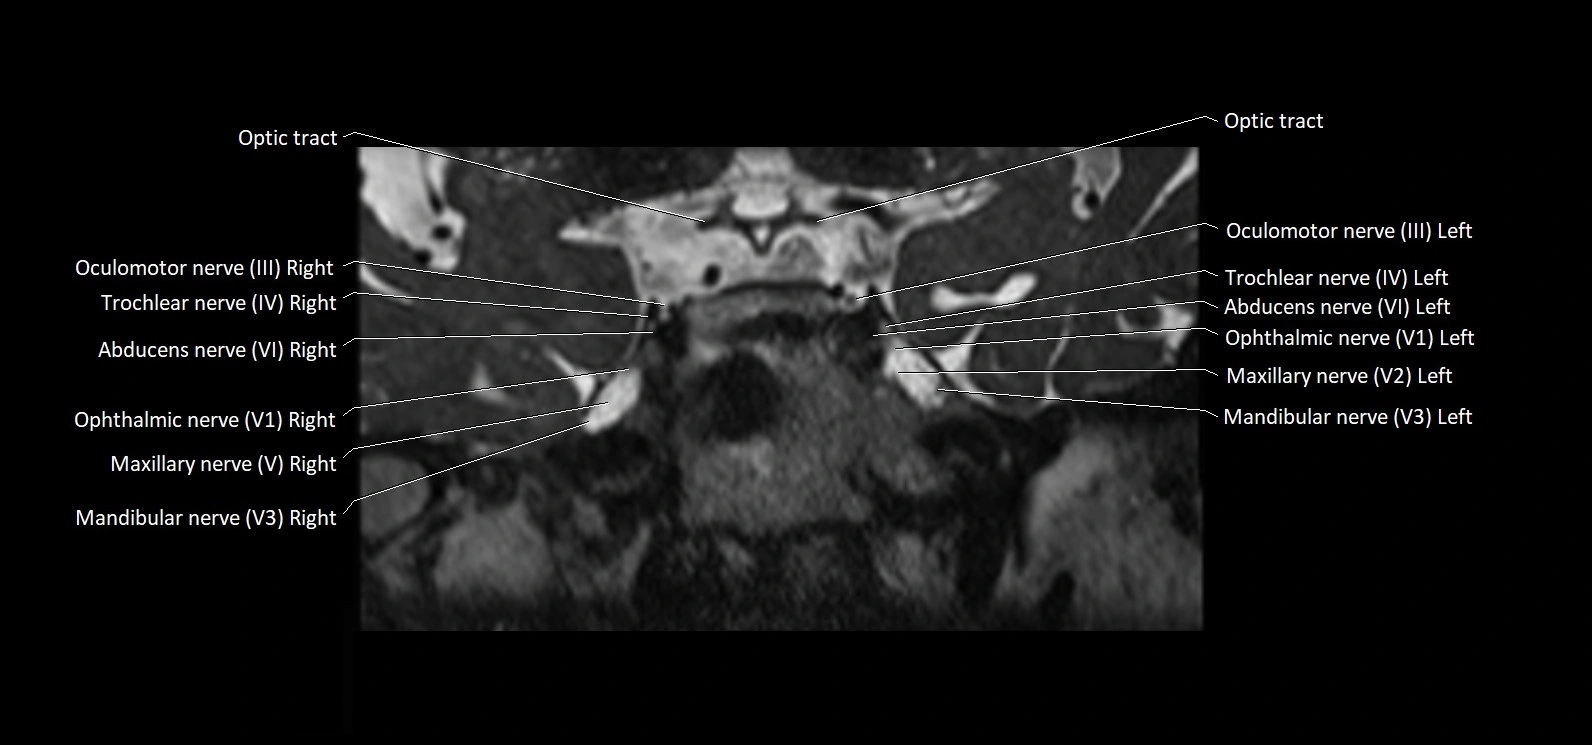

MRI Appearance

• The abducens nerve is a small, thin, linear structure

• Best visualized on high-resolution T2-weighted 3D MRI sequences (e.g., FIESTA or CISS)

• Seen as a hypointense (dark) line running from the brainstem at the pontomedullary junction, traversing the prepontine cistern, and entering Dorello’s canal under the petrosphenoidal ligament, then into the cavernous sinus, and finally the orbit

• May be challenging to visualize in standard MRI due to its small size

• Pathology may be inferred by absence, displacement, or enhancement of the nerve

MRI images

image